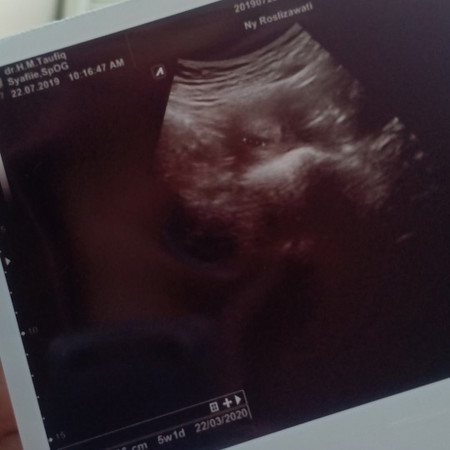

USG

Bunda mau tanya sy habis USG baru keliatan kantong kecil. Apakah normal ? Dan Menurut dokter UK nya sudah 5 minggu 1 hari Sedangkan perkiraan sendiri masih 4 minggu 4 hari

Normal bun. Sy dulu 4w jg baru keliatan kantong kehamilan aja. Ntar usia 8-10w USG lg buat mastiin kehamilannya jadi atau kosong.